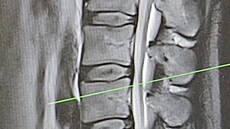

„Dostávám silné kapačky, užil jsem si svou oblíbenou magnetickou rezonanci během neděle a probíhá už i fyzioterapie. S léčbou jsem začal ve čtvrtek po návratu ze státní návštěvy v Bratislavě. Začátkem příštího týdne bych měl mít ještě jeden drobný zákrok, abych se vyhnul operaci, která časem asi bude nutná, ale rekonvalescence by nyní byla příliš dlouhá. Kdy budu z nemocnice propuštěn, to neumím odhadnout,“ vzkázal nám.